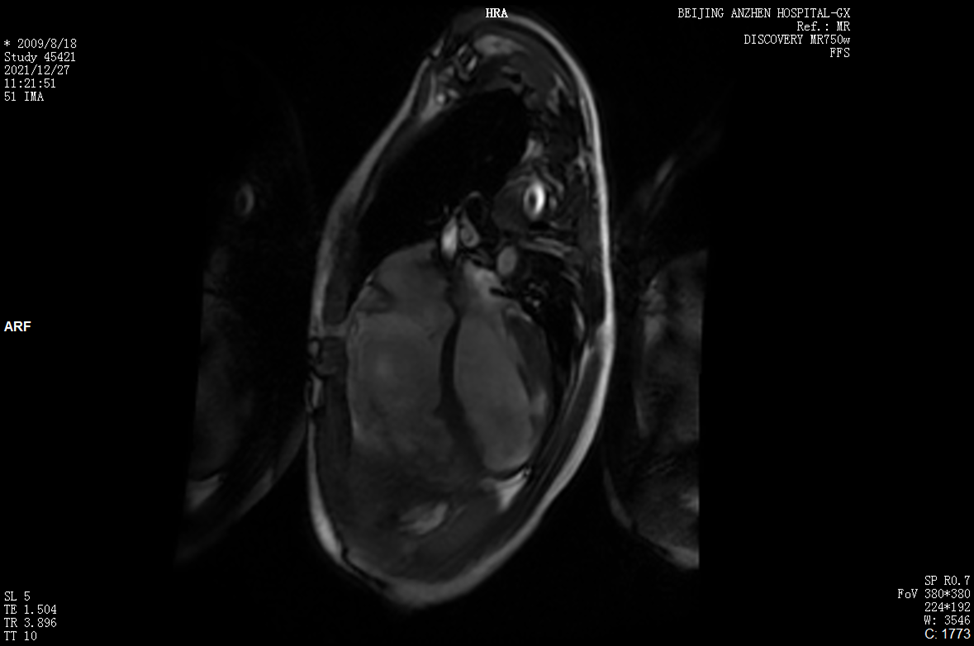

心脏磁共振成像

LVEDD 42.6 m,RVEDD 51.4 mm;RVOT前后径38.3 mm。

MRI:双室壁变薄,右室游离壁及左室心尖多发瘤样膨出,左室壁运动减低、不协调,舒张明显受限,收缩功能减低。

心肌延迟成像:右室游离壁、左室心外膜下心肌及间隔壁内条形延迟强化。

左心功能:LVEF 33.67%;右心功能:RVEF 32.35%,EDV 210.95 ml(RVEDV/BSA=142 ml/m2)。